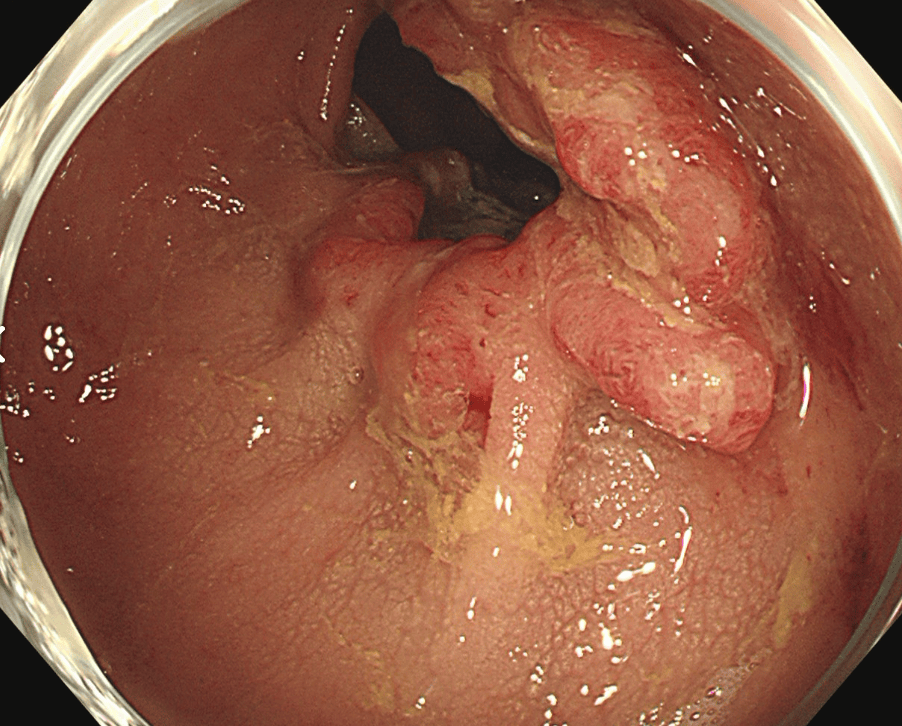

内視鏡的切除

肛門から挿入したスコープ(カメラ)でがんのある部位を切除します。おなかを切ることがないため、術後の痛みがほぼなく、入院期間も短かく済みます。がんが粘膜内にとどまっている場合のみ適応があり、それよりも進行している場合は手術をはじめとした他の治療が行われます。

閉塞性大腸がんに対する大腸ステント治療

大腸がんが進行し腸が詰まってしまう閉塞性大腸がん(大腸がん腸閉塞)に対する治療です。従来は人工肛門を造設して対処していましたが、人工肛門はケアの負担やにおいに対する不安などからQOL(生活の質)低下が避けられません。そのため当院ではステントと言われるメッシュ構造の金属製の網を用いて詰まりを解消し、人工肛門を回避する治療を行っています。大腸ステント治療は緩和治療を目的に行う場合と根治手術前に全身状態の回復を目的として行う場合があります。

治療前